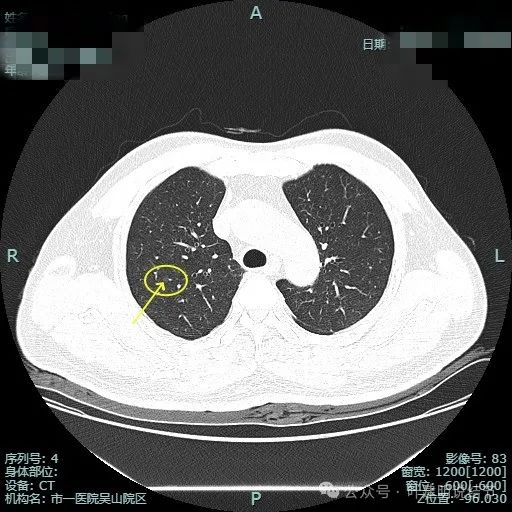

先看非薄层影像:

左上病灶出现,密度较淡,但轮廓较清。

密度不纯,有明显分叶。

有血管异常增粗与进入,边缘有细毛刺征。

血管穿行与表面浅分叶。